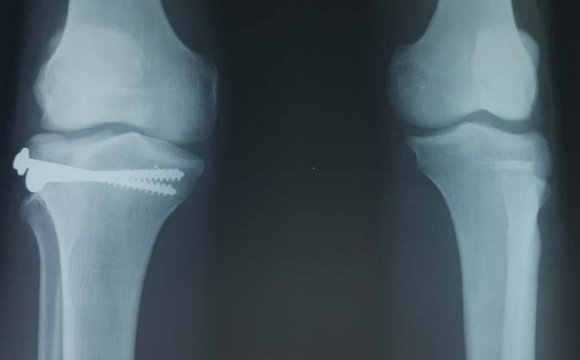

Plain radiographies of the lower extremities were performed: they showed medial right knee dislocation with ipsilateral type 42 A2 tibial shaft fracture and fracture dislocation of the left knee.

In the operation room, exploration of the knees' injury revealed: in the right knee a section of the biceps femoris, broises in the common peroneal nerve and the ACL and the PCL were intact, in the left knee, no noble element was affected. The fracture was fixed with srews.

Internal fixation of the tibial and fibular shaft were performed. The patient had bilateral knee immobilization for 45 days. Then, he begun rehabilitation. The consolidation fracture was obtained after 04 months.